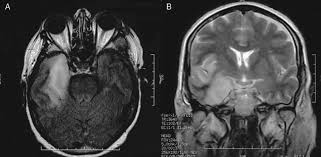

We describe the spectrum of etiologies associated with temporal lobe (tl) encephalitis and identify clinical and radiologic features that distinguish herpes simplex encephalitis (hse) from its mimics.

Watershed distribution ischemia in areas remote from the primary herpetic lesions may be seen. Herpes simplex encephalitis typically manifests in older adults (about 50% of cases) with headache, fever, altered sensorium, and even seizure. Hippocampus, temporal lobe, and the ponsfigure 4a.7. Herpes simplex virus (hsv) is the most common cause of acute fatal sporadic encephalitis, with a particular predilection for the limbic system. Unfortunately, the imaging findings are often nonspecific with overlapping appearances. This lesion was seen in all patients as the disease progressed. Severe edema, petechial hemorrhage, and massive hemorrhagic tissue necrosis can be seen on gross specimens. He was managed with intravenous acyclovir 30mg/kg and supportive therapy. that appeared in a recent issue of clinical infectious diseases. However, mimics of hse, including other infections and increasingly recognized autoimmune causes, have been described in cases of tl encephalitis. But changes are not specific for hsv (e.g. The characteristic feature of hse is hemorrhagic necrosis of the temporal lobe. The basal ganglia are usually spared.

It is usually bilateral but asymmetrical. This lesion was seen in all patients as the disease progressed. Two subtypes are recognised which differ in demographics, virus, and pattern of involvement. The lateral temporal lobe and insula are less commonly involved, whereas the basal ganglia, in contrast, are frequently involved, helpful in distinguishing it from hsv encephalitis which characteristically spares the basal ganglia 8. However, mimics of hse, including other infections and increasingly recognized autoimmune causes, have been described in cases of tl encephalitis. Severe edema, petechial hemorrhage, and massive hemorrhagic tissue necrosis can be seen on gross specimens. Because early diagnosis is possible in more cases of herpes simplex encephalitis (hse) as a result of the high sensitivity of mri, now widely available, a larger number of patients are receiving appropriate treatment with iv acyclovir. A feasibility study of quantifying longitudinal brain changes in herpes simplex virus (hsv) encephalitis using magnetic resonance imaging (mri) and stereology. In addition, it was observed in various pathological conditions: Limbic encephalitis, mca ischaemia, tumours, effects of seizures) hyperintense t2 signal in the medial temporal lobes, inferior frontal lobes and insula basal ganglia are usually spared He was managed with intravenous acyclovir 30mg/kg and supportive therapy. We describe the spectrum of etiologies associated with temporal lobe (tl) encephalitis and identify clinical and radiologic features that distinguish herpes simplex encephalitis (hse) from its mimics. Herpes simplex virus (hsv) is the most common cause of acute fatal sporadic encephalitis, with a particular predilection for the limbic system.